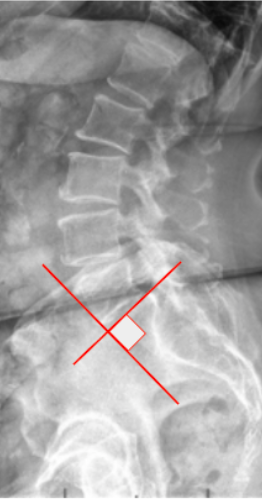

Ullmann’s Line is a radiographic parameter used to evaluate anterior vertebral translation (spondylolisthesis) at the lumbosacral junction (L5–S1).

It serves as a simple geometric reference for detecting anterior slippage of L5 relative to the sacrum by assessing the alignment between the L5 vertebral body and the sacral base.

• Sacral Base Line: Extend a line along the superior surface of S1.

• Perpendicular Line: Draw a line perpendicular to the sacral base line at its anterior corner.

• Evaluate the position of the anterior-inferior corner of L5 relative to this perpendicular line:

• Normal: The anterior-inferior corner of L5 is posterior to or just touches the perpendicular line.

• Abnormal: If the L5 anterior-inferior corner crosses anteriorly beyond this line, it indicates anterior translation (spondylolisthesis).